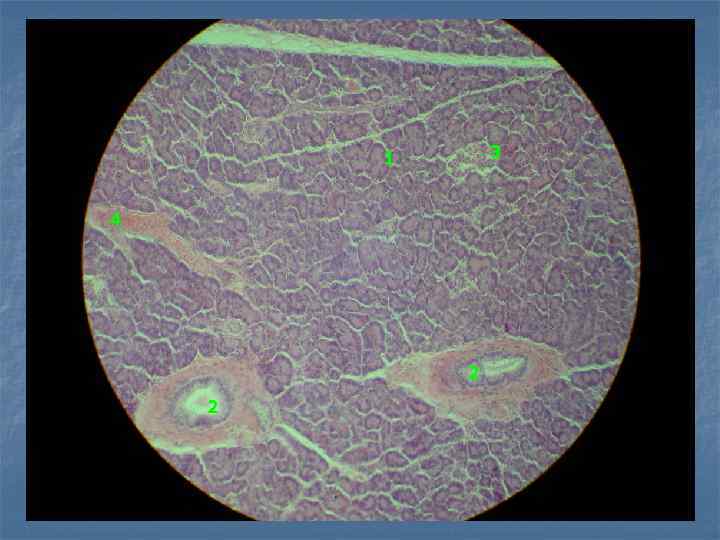

Пр. 2. Печень человека. Окраска: гематоксилин и эозин. Увеличение: малое. печеночные балки центральная вена междольковый желчный выводной проток междольковая артерия междольковая вена синусоидные капилляры

3 1 4 2 2